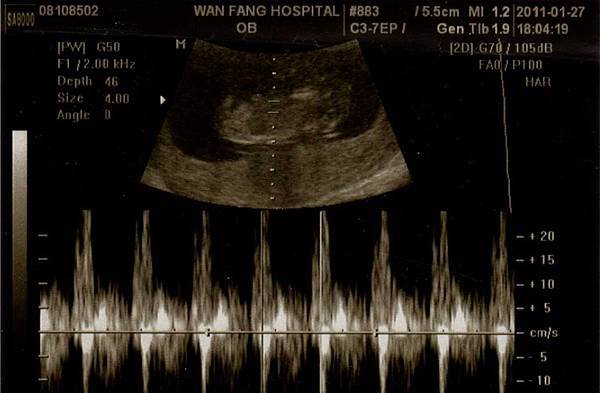

這是還在肚子裡時,11週5天的小摸。只有5cm,像顆豌豆。